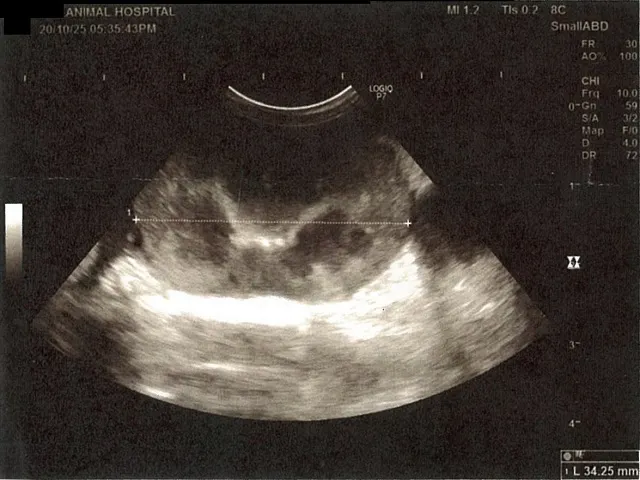

膀胱周りに腹水が確認できるエコー写真

心臓のみ腹水が確認できないエコー写真